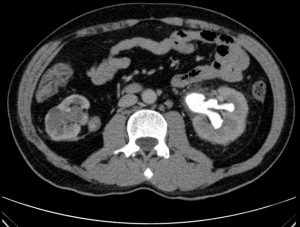

A male patient, 51 years old, native of Manaus, reports dysuria and polyuria associated with constant fever episodes and urinary tract infections with improvement by using several antibiotics but returning the symptoms after suspending it; evolving over a year with left flank and back pain and spreading out to the left inguinal region and testicle associated with anemia displayed at routine exams. The patient reports a surgical treatment 12 years ago for treating a staghorn calculus in the right kidney with similar symptoms, at the time in another hospital, but without further medical assistance after the procedure, even though claiming an improvement of the symptoms. He denies drug allergies, familiar history of calculus and cancer or any other comorbidities. He confirmed that after the first episode of staghorn calculi, he increased water intake, but did not maintain the same way over time. Six months after the beginning of his condition, during an ambulatory visit, it was requested a complete abdominal tomography with emphasis in the urinary system, blood and urine tests for clinical association, in addition to non-steroidal anti-inflammatory medicines. The patient return was in a month and no improvement of the pain in the patient’s feeling, with the tomography image tests result showing atrophy in the right kidney, which presents dilatation of the collector system, that it’s filled with material with density varying between thick liquid and soft parts (average of 45 UH), in addition to calculus in the pelvis and ureteropelvic junction, suggesting a pattern for xanthogranulomatous pyelonephritis and matching previous history of right staghorn calculus (Figure 1). The left kidney presented normal dimensions, exophytic nodule in the lower pole measuring 3.4 cm × 2.8 cm with contrast enhancement similar to renal parenchyma, associated with a simple cortical cyst and a large staghorn calculus (6.0 cm × 3.5 cm) in this kidney, with average density of 300 UH, 7.7 cm distant from the pelvis, causing dilatation of superior caliceal group in this kidney. Presented abnormal test results for urea with 109 mg/dL and creatinine with 4.4 mg/dL. It was decided for partial left nephrectomy and total right nephrectomy, considering that it had significant hydronephrosis, a relevant decrease in the parenchyma and, mainly, being an infectious focus. The patient also had history of several episodes of urinary infection resistant to antibiotics, presenting potential risk of sepsis. The incision made was bilateral subcostal, followed by exploration and control of right renal hilum. The right kidney presented with hydronephrosis, although with rigid consistency and intense inflammatory process. Total right nephrectomy was performed. After that, partial left nephrectomy began, with isolation and controlling of the left renal hilum vessels, performing for excision of the renal nodule of the upper pole, followed by anatrophic nephrolithotomy with Brödel’s line incision, that revealed great purulent discharge escape (about 500 milliliters) (Figures 2-4). Staghorn calculus was removed with double-J stent implanted in left ureter and layer suture performed. The surgery went through eight hours and was attended by nephrology service of the same hospital. In the following four days after the procedure, the patient was maintained under observation in the intense therapy unity, performing dialysis every two days, with progressive improvement of the pain and operative wound with great appearance. The left renal function showed constant increasing during the dialysis. On the fifth post-operative day, the patient returns to the urology nursery care with renal function still impaired but presenting diuresis of 1,500 milliliters per day on average. In the seventh day presented obvious hematuria by Foley catheter, needing a successful bladder washing. The patient was discharged from hospital in the 12th post-operative day with pain improvement and clear renal function progress, not needing continuous post-operative dialysis. The anatomopathological examination of the left kidney showed renal cell carcinoma, clear cell type, with nuclear grade of Führman 1, measuring 25 cm in larger diameter (5) (Figure 5). The right kidney just showed hydronephrosis without neoplasms signs.